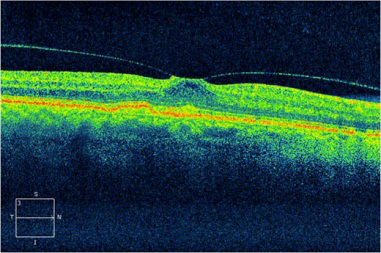

玻璃體視網膜,?,斎鹨曆劭?上海眼科醫院

(OCT檢查顯示眼睛的黃斑前膜,纖維膜在黃斑表面產生牽拉的力量,可引致黃斑水腫或裂孔,引致視野中央出現暗點)